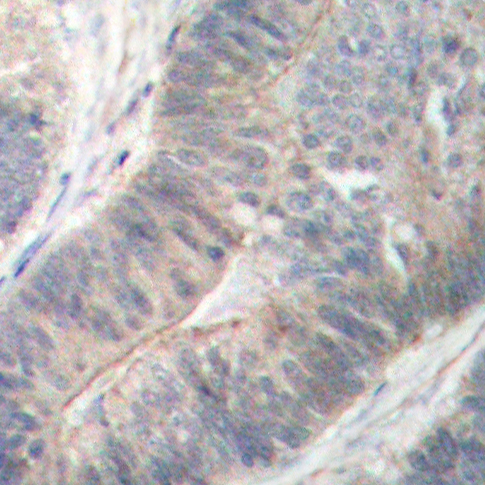

• AP0340: image 1

Immunohistochemical analysis of paraffin-embedded human colon carcinoma tissue using Phospho-EIF2AK2-T451 antibody.